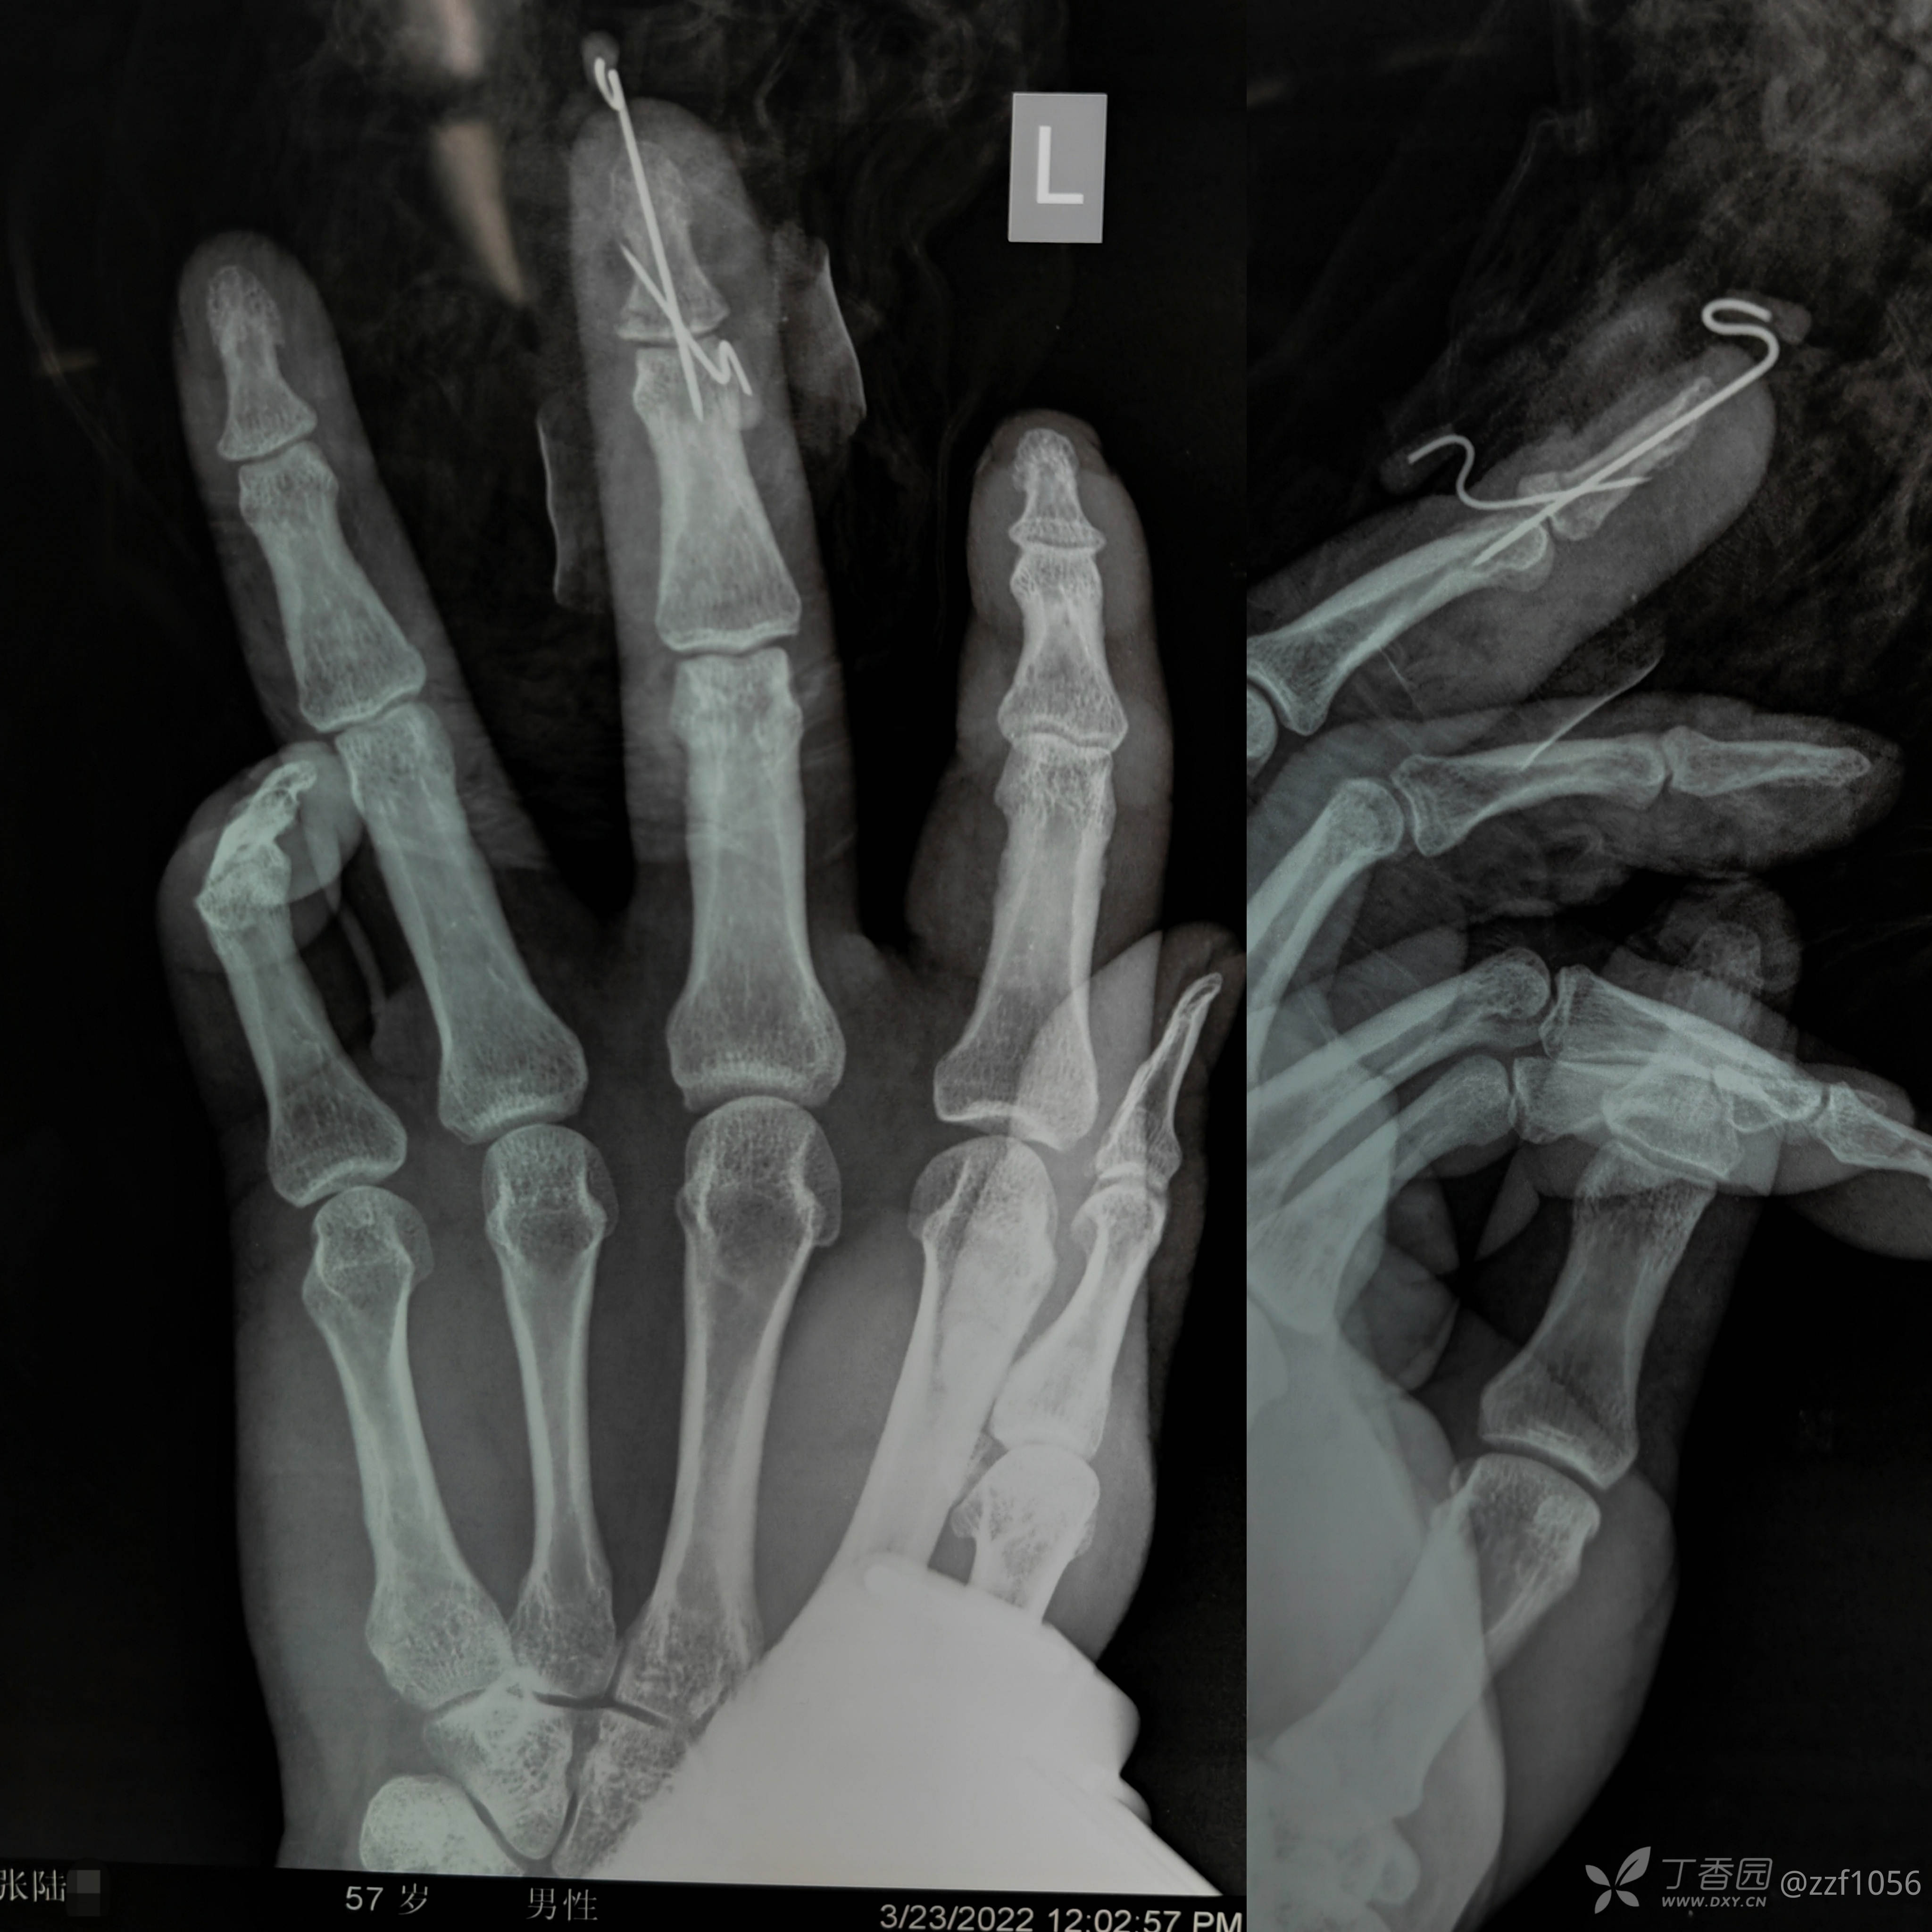

复位后植入内固定

清理好的指甲板

指甲回植后缝合固定

甲板上敷料块微加压

因基底粉碎临时固定了dip,不建议常规固定关节

石膏与指夹板非必须固定,术者酌情把握